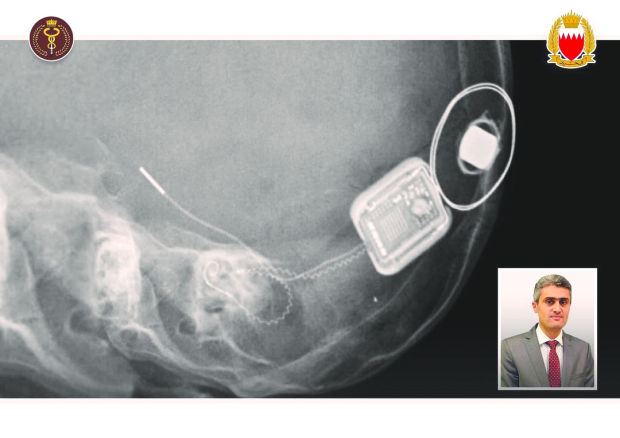

A cochlear implant operation for a girl aged one year and 10 months was successfully performed at the King Hamad University Hospital.The operation, led by consultant and ear, nose and throat surgeon Dr Omar Sabra, and his team was held in co-operation between the Royal Medical Services, King Hamad University Hospital and Al Mabarrah Al Khalifia Foundation .